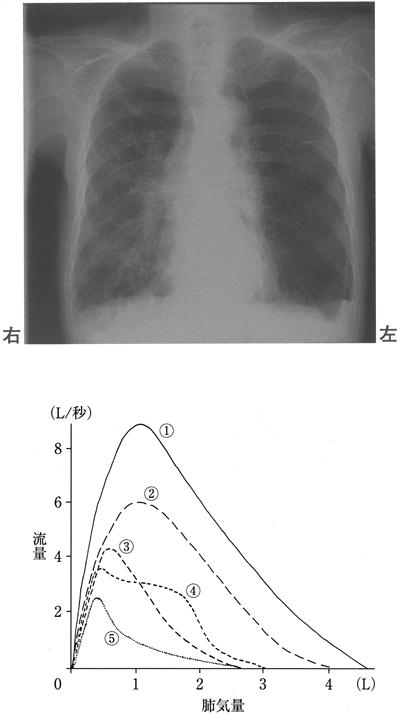

この問題では、呼吸器疾患に関する正しい情報を選択する必要があります。正しい選択肢は3で、気管支喘息の発作時に1秒率が低下することです。

選択肢別解説

肺線維症は閉塞性肺疾患ではなく、拘束性肺疾患です。間質性肺炎の終末像で、肺が縮小した状態になります。

気管支拡張症では、乾性咳嗽ではなく、湿性咳嗽がみられることが一般的です。亜区域気管支より末梢部分が非可逆的に拡張した状態になります。

選択肢3は正しいです。気管支喘息は、気道の慢性炎症性疾患で、閉塞性肺疾患に分類されます。そのため、発作時には1秒率が低下します。

過換気症候群では、呼吸性アシドーシスではなく、呼吸性アルカローシスになります。精神的な不安によって過呼吸になり、二酸化炭素の排出量が増加し、アルカローシスが生じます。

CO2ナルコーシスは、低CO2血症ではなく、高CO2血症によって生じます。肺機能の低下により換気量が減り、血液中の二酸化炭素濃度が著しく上昇することで症状が現れます。